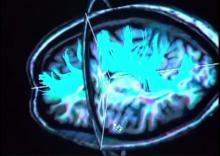

Some high school football players exhibit measurable brain changes after a single season of play even in the absence of concussion, according to a study presented at the annual meeting of the Radiological Society of North America (RSNA).